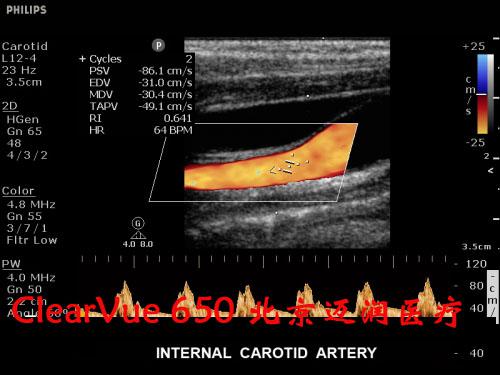

飛利浦ClearVue?CV650彩超

飛利浦ClearVue CV650(HD11XE升級版)是集成了飛利浦多項先進超聲技術(shù)的全身應(yīng)用型實時三維彩色超聲診斷系統(tǒng),采用了飛利浦最新的“元設(shè)計”理念。在原始信號的采集上,CV650飛利浦專利的超聲探頭微信號處理技術(shù)(雙A探頭技術(shù)),保證了零損耗寫真級實時數(shù)據(jù)采集,呈現(xiàn)更真實的圖像信息,可以大大減少臨床上的誤診與漏診的發(fā)生率。

對實時三維功能而言,CV650是飛利浦CV系列產(chǎn)品“維時代”的開端。

良好的二維成像技術(shù)是保證實時三維圖像質(zhì)量的關(guān)鍵。CV650的實時三維成像融合了飛利浦傳統(tǒng)的優(yōu)勢技術(shù)SONOCT和Xres,保證了良好的圖像分辨力和對比度;另外,容積探頭也采用了“雙A探頭技術(shù)”,能夠?qū)崿F(xiàn)原始信號的零損耗,使呈現(xiàn)的三維圖像效果更逼真。同時,高速的處理內(nèi)核能使容積探頭實現(xiàn)最大48幁/秒的掃描速率,完成一次靜態(tài)掃描的時間也只需要2秒鐘,這些都保證了容積成像的可操作性。

在實時三維應(yīng)用上,CV650配備了胎兒面部自動識別軟件,全新的胎兒面部信息數(shù)字鑒定技術(shù),能夠一鍵清除遮擋物,使胎兒面部結(jié)構(gòu)尤其是異常缺陷能夠瞬間清晰顯示,大大便捷了醫(yī)生對胎兒面部的掃查過程。鑒于基層醫(yī)院對于胎兒心臟先天性疾病診斷能力的不足,這款機器還配備有STIC成像功能,簡單的操作、快速的圖像獲取、強大的離線分析能夠保證準確高效地獲取胎心不同標準切面,是基層超聲醫(yī)生診斷胎兒先心病的利器。

該設(shè)備凝聚了前沿的圖像處理技術(shù)和實用的臨床解決方案,ClearVue CV650適用于腹部、婦產(chǎn)科、小器官、兒科、心臟、外周血管、泌尿系、肌肉骨骼以及術(shù)中檢查和介入診斷治療。

飛利浦ClearVue 650超聲系統(tǒng)臨床高清圖片